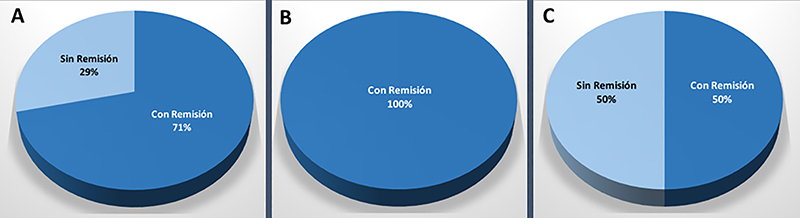

Gráfico 3: Resultados en pacientes acromegálicos. A: Remisión bioquímica global. B: Remisión bioquímica en el caso de los microadenomas. C: Remisión bioquímica para los macroadenomas.

En los pacientes con enfermedad de Cushing (n=26), de los cuales 19 eran microadenomas y 7 macroadenomas, se logró con la cirugía una tasa de remisión bioquímica global del 81% (n=21); siendo la remisión para microadenomas del 84% (n=16) y para macroadenomas del 71% (n=5) (graf. 4). Los pacientes sin remisión se encuentran bajo terapia multimodal.

Gráfico 4: Resultados en pacientes con Enfermedad de Cushing. A: Remisión bioquímica global. B: Remisión bioquímica en el caso de los microadenomas. C: Remisión bioquímica para los macroadenomas.

En los pacientes con prolactinomas (n=21), de los cuales 9 fueron microadenomas y 12 macroadenomas, se logró con la cirugía una remisión bioquímica global del 71% (n=15); siendo la remisión para microadenomas del 100% (n=9) y para macroadenomas del 50% (n=6) (graf. 5). Los 6 pacientes con hiperprolactinemia activa se encuentran en seguimiento bajo tratamiento multimodal. De estos, 4 pacientes presentaron un Knosp alto preoperatorio.

Gráfico 5: Resultados en pacientes con prolactinoma. A: Remisión bioquímica global. B: Remisión bioquímica en el caso de los microadenomas. C: Remisión bioquímica para los macroadenomas.

En los pacientes acromegálicos (n=52), de los cuales 21 fueron microadenomas y 31 macroadenomas, se logró con cirugía una tasa de remisión global del 75% (n=39); siendo la remisión para microadenomas del 95% (n=20) y para macroadenomas del 61% (n=19) (graf. 3). En los pacientes que no se logró remisión con cirugía, se registró un Knosp alto en el preoperatorio en todos los casos (n=13). Estos últimos se encuentran bajo terapia multimodal.

En la literatura mundial las tasas de remisión bioquímica global en acromegalia van del 42 al 83%.4,11,28,30,32,33,37,39,42,50,52,53,56,58 Nosotros obtuvimos una tasa de remisión global del 75%, valor que se encuentra dentro del rango obtenido por centros internacionales especializados.

Nomikos et al. encontró una correlación significativa entre tamaño del adenoma y tasa de remisión: 75,3% en microadenomas, 48,6% en macroadenomas y 8,3% en gigantes.49 Jane et al, en un estudio multicéntrico, describe una tasa de remisión del 100% para microadenomas, 61% para macroadenoma y 45,5% para los mayores a 2 cm.37 En nuestra serie se logró la remisión en 95% de los microadenomas y 61% de los macroadenomas, lo que se asemeja a esto último.

Finalmente, cabe destacar que diversos estudios mutivariados6,47,59 concluyen en que la invasión del seno cavernoso es un predictor de no-remisión. En este sentido, el equipo de Erlagen demostró que las tasas de remisión que obtuvieron del 72,2% en adenomas no-invasivos, cayeron a un 21,6% en los invasores.49 En nuestra serie, en la totalidad de pacientes acromegálicos sin remisión (25%, n=13) se evidenció un Knosp alto.

Enfermedad de Cushing

En nuestra serie se alcanzó una tasa de remisión: global del 81%, para microadenomas del 84% y para macroadenomas del 71%. La tasa global y para microadenomas es equiparable a la publicada por equipos de referencia. La alta tasa de remisión en macroadenomas respecto a la literatura se explica por un sesgo estadístico (N reducido de pacientes con macroadenoma y enfermedad de Cushing).

Prolactinomas

En el pasado se discutía “tratamiento médico versus cirugía”; actualmente el tratamiento con agonistas dopaminérgicos se constituye como la primera línea y las indicaciones quirúrgicas se limitan a situaciones muy especificas.9 Sin embargo, un grupo significativo de pacientes finalmente son intervenidos quirúrgicamente por diversas causas (E.G. resistencia, intolerancia y reacciones adversas del tratamiento médico).36 De estos pacientes que son operados, analizaremos sus resultados.

Respecto a la tasa de remisión global, Jho et al. reportaron un 71%.38 En cuanto a la tasa de remisión según el tamaño, en una compilación de series publicadas, la tasa de normalización de PRL fue de 83% en microprolactinomas57 y 45.1% en macroprolactinomas1.

De lo antes expuesto, queda en evidencia que la cirugía ofrece excelentes resultados de tasa de normalización de prolactina en el caso de los microprolactinomas.9

Los pacientes con mayores chances de remisión son quienes presentan: niveles de PRL menores a 200 µg/l, tumores pequeños y amenorrea de corta duración. El hecho de tratarse de un macroadenoma disminuye cuantitativamente las probabilidades de remisión; y el hecho de tener extensión al seno cavernoso prácticamente la anula.21

El equipo de Viena, sostiene que la localización del tumor respecto a la glándula pituitaria es un factor asociado a remisión en microprolactinomas. En un reciente estudio, reportan una tasa de remisión en los adenomas centrales a la glándula significativamente mayor a la de los adenomas laterales a la glándula (87% vs 45%).46

En la presente serie la tasa de remisión global fue del 71%; mientras que la tasa de remisión según tamaño fue 100% para microadenomas y 50% para macroadenomas. Estas cifras pueden homologarse a la de las publicaciones enunciadas en este apartado. La alta tasa de normalización de la PRL obtenida en microprolactinomas se explica debido a que estos pacientes presentaron tumor central a la glándula y no lateralizado.